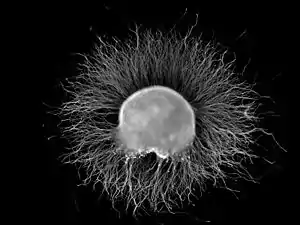

| Ganglion | |

A ganglion (pl.: ganglia) is a group of neuron cell bodies in the peripheral nervous system. In the somatic nervous system, this includes dorsal root ganglia and trigeminal ganglia among a few others. In the autonomic nervous system, there are both sympathetic and parasympathetic ganglia which contain the cell bodies of postganglionic sympathetic and parasympathetic neurons respectively.

Ganglia are primarily made up of somata and dendritic structures, which are bundled or connected. Ganglia often interconnect with other ganglia to form a complex system of ganglia known as a plexus. Ganglia provide relay points and intermediary connections between different neurological structures in the body, such as the peripheral and central nervous systems.